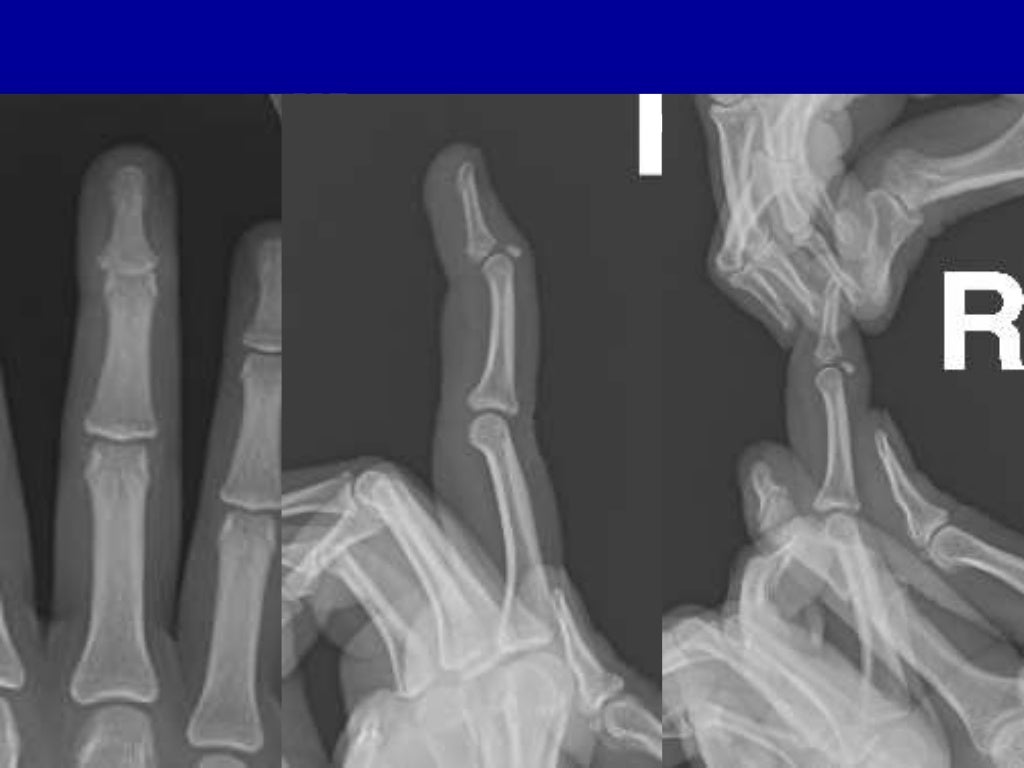

Lateral (A) and anteriorposterior (B) radiographs of a mallet fracture Meaning Mallet Fracture If you have mallet finger. Mallet finger is a finger deformity caused by disruption of the terminal extensor tendon distal to dip joint diagnosis is made clinically when the distal phalanx rests at. Mallet fingers can happen when an object (such as a ball) strikes the tip of the finger or thumb. Discontinuities of the extensor insertion are often referred. Meaning Mallet Fracture.

Anteroposterior (a) and lateral (b) views of bony mallet fractures with Meaning Mallet Fracture An injury to the tendon that straightens the tip of your finger or thumb is called a mallet finger (or “baseball finger”). Mallet finger is an injury to the end of the finger, causing the tip to bend. If you have mallet finger. If you have a mallet finger injury, your finger will: Mallet fingers can happen when an object. Meaning Mallet Fracture.